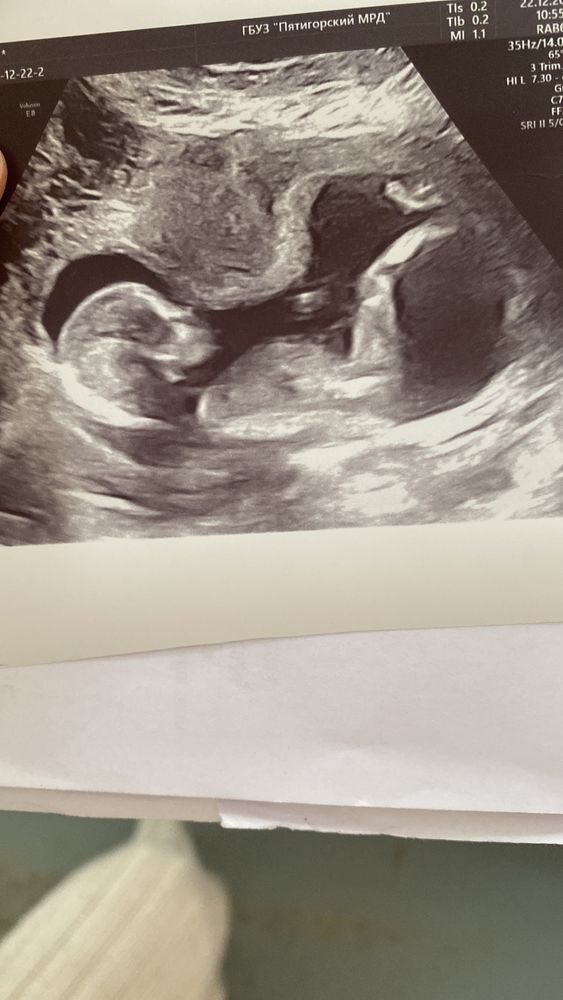

Вот фото с узи)Какого пола ребенок,как бы вы подумали?16 недель)фото снизу)

02.06.2017

Я как будто бы вижу мошонку, поэтому склоняюсь к мальчику, но неточно. У Вас вроде голубой кружок был?